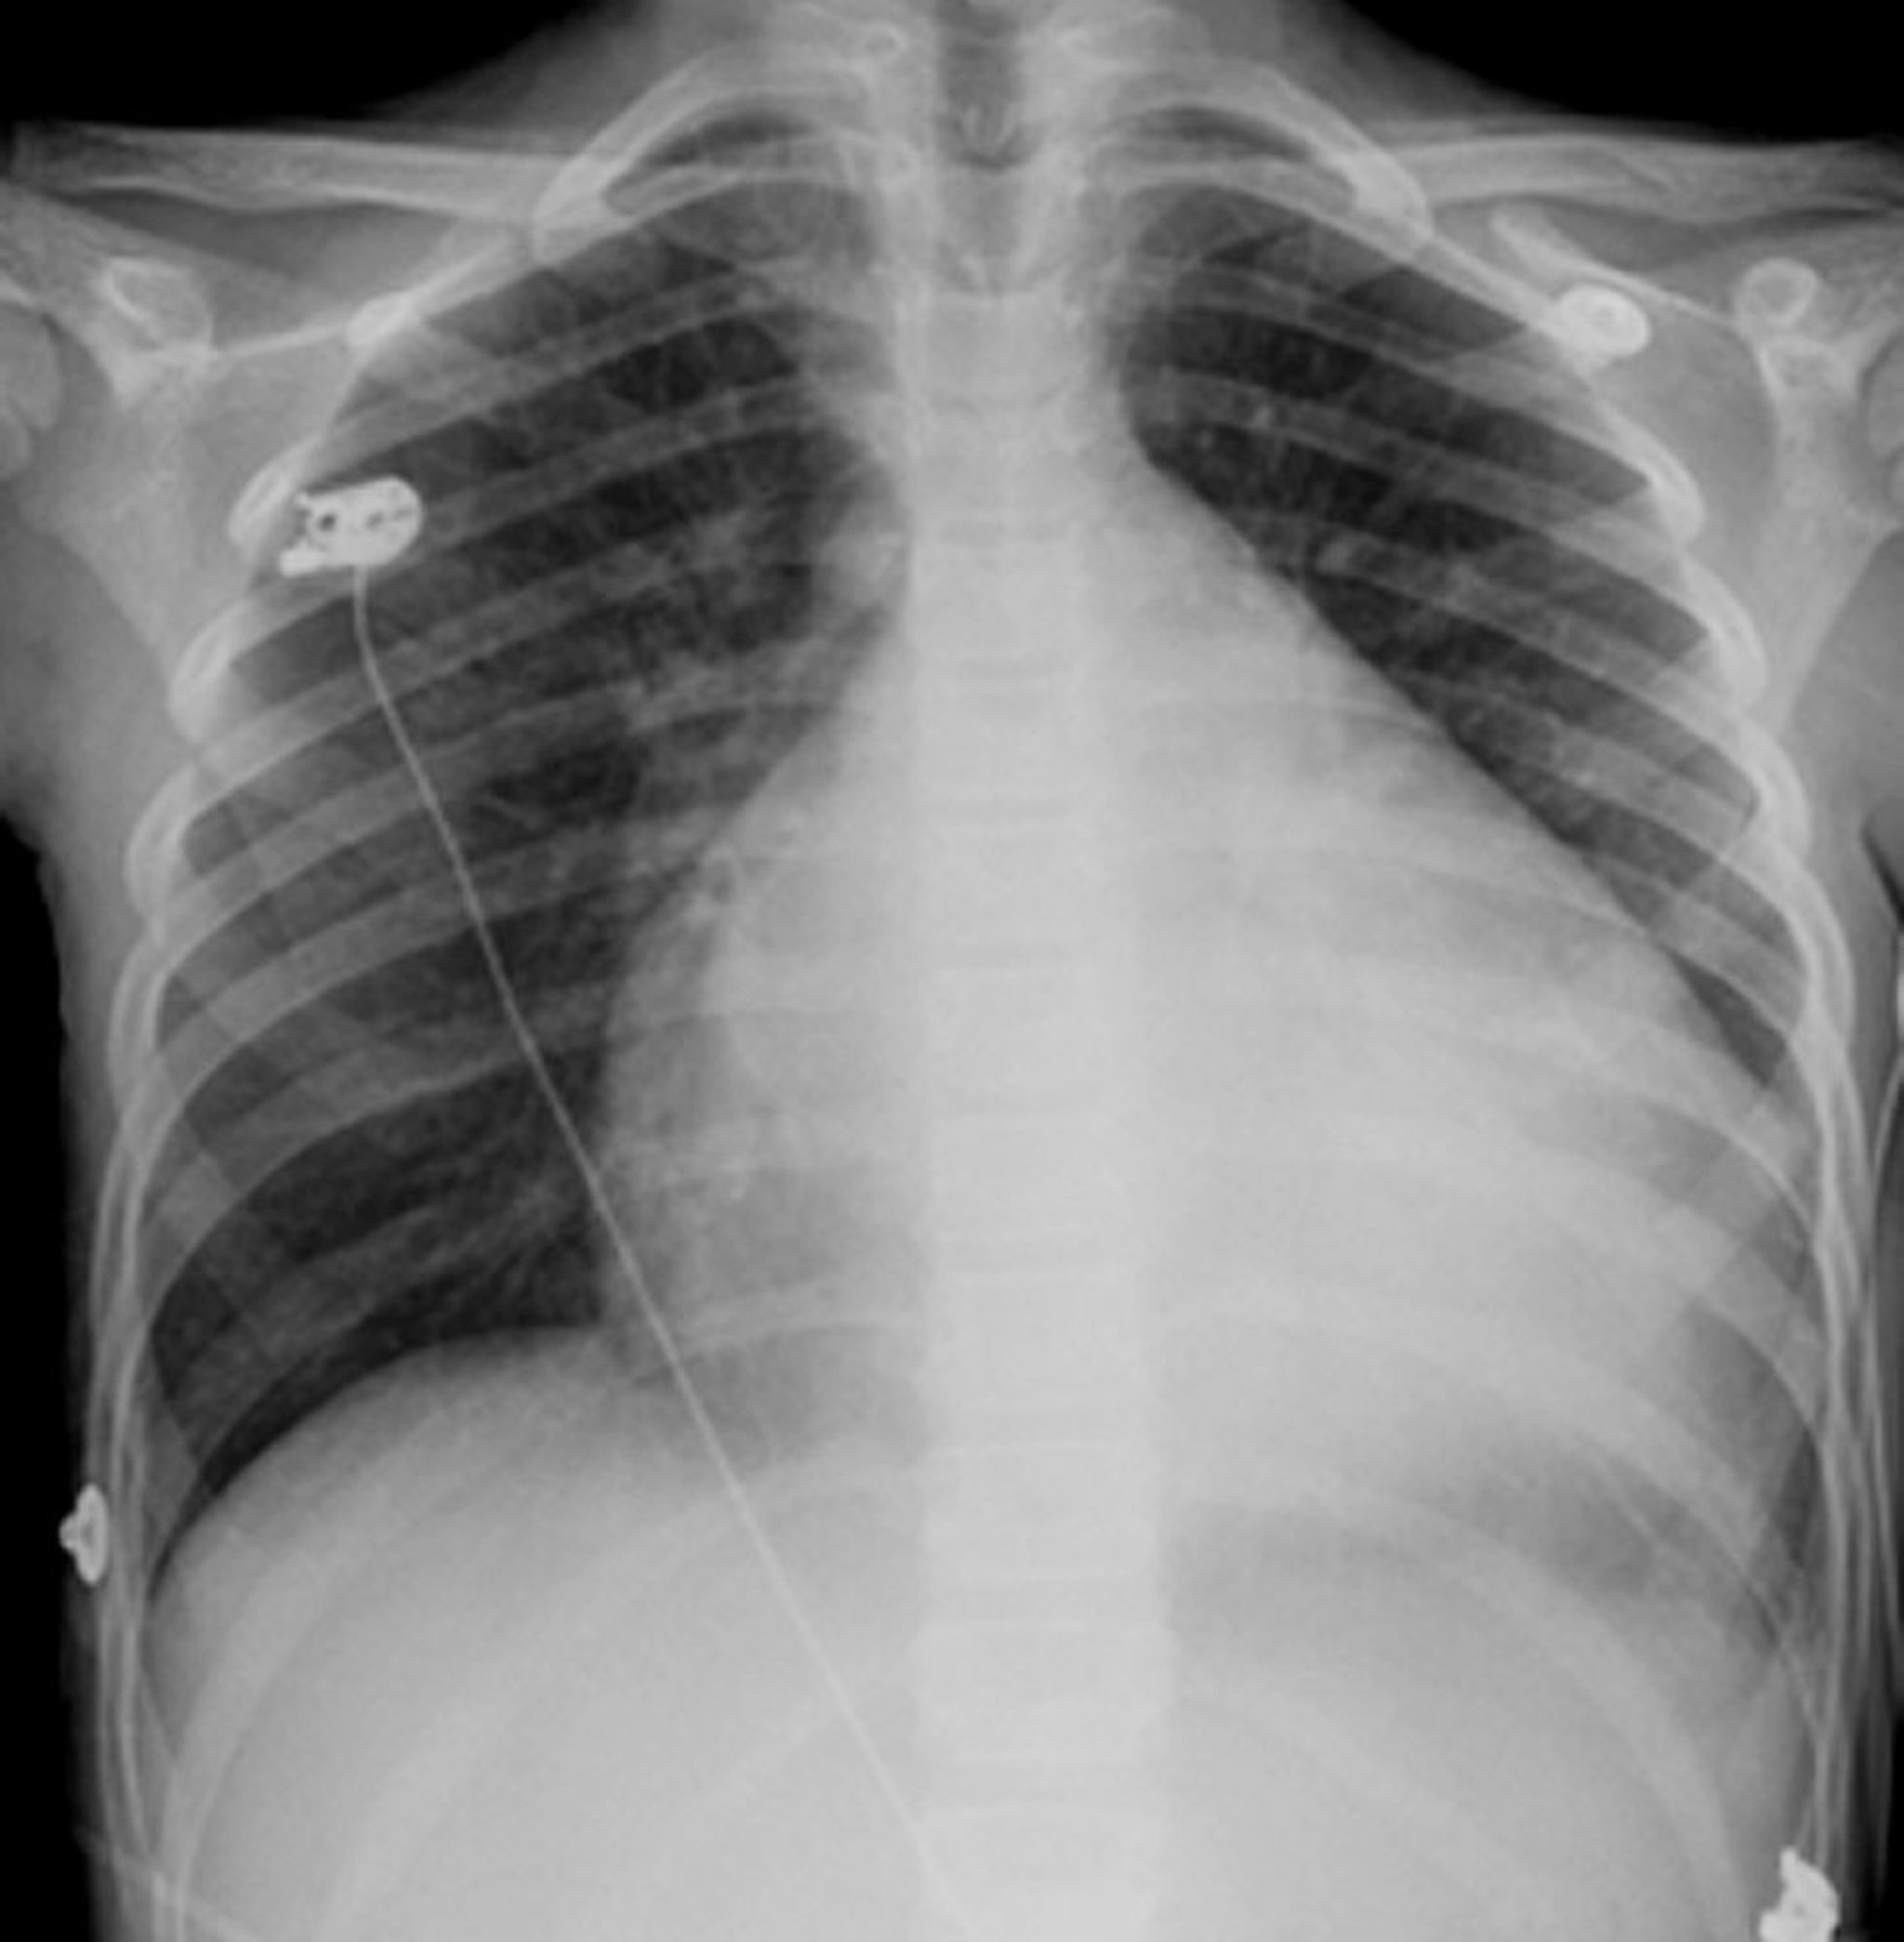

Cardiomiopatia dilatativa (radiografia del torace)

Questa radiografia mostra una grave cardiomegalia in un paziente con cardiomiopatia dilatativa.